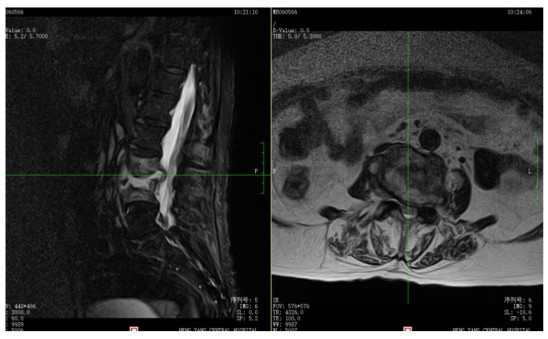

為解決老人病痛���,脊柱外科錢軍博士團(tuán)隊(duì)對(duì)其進(jìn)行了詳細(xì)的查體以及全面細(xì)致的評(píng)估�����,診斷為L3�����、4脊柱結(jié)核伴病理性骨折���、椎旁膿腫����,患者腰部疼痛癥狀逐漸加重�,病灶已經(jīng)壓迫神經(jīng)引起了截癱�。